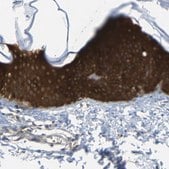

immunohistochemistry: 1:200-1:500

The Human Protein Atlas project can be subdivided into three efforts: Human Tissue Atlas, Cancer Atlas, and Human Cell Atlas. The antibodies that have been generated in support of the Tissue and Cancer Atlas projects have been tested by immunohistochemistry against hundreds of normal and disease tissues and through the recent efforts of the Human Cell Atlas project, many have been characterized by immunofluorescence to map the human proteome not only at the tissue level but now at the subcellular level. These images and the collection of this vast data set can be viewed on the Human Protein Atlas (HPA) site by clicking on the Image Gallery link. We also provide Prestige Antibodies® protocols and other useful information.

- IHC tissue array of 44 normal human tissues and 20 of the most common cancer type tissues.